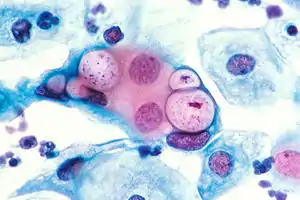

| Pap smear showing C. trachomatis (H&E stain) | |

Under magnification of 50X, a McCoy cell monolayer culture, and that some of the cells exhibited Chlamydia trachomatis inclusion bodies. Using cell cultures from the McCoy cell line is one methods implemented in diagnosing Chlamydia infections.

Under magnification of 50X, a McCoy cell monolayer culture, and that some of the cells exhibited Chlamydia trachomatis inclusion bodies. Using cell cultures from the McCoy cell line is one methods implemented in diagnosing Chlamydia infections. Chlamydia trachomatis inclusion bodies (brown) in a McCoy cell culture